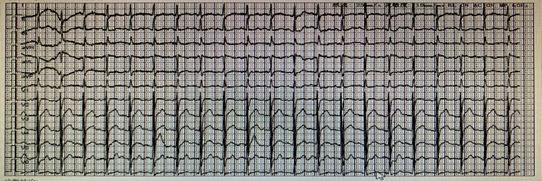

Figure 1 The electrocardiogram on November 8, 2020.

The electrocardiogram was performed after admission in Jinyang Hospital, results showed that Sinus tachycardia(140/min)and mild change of T wave.